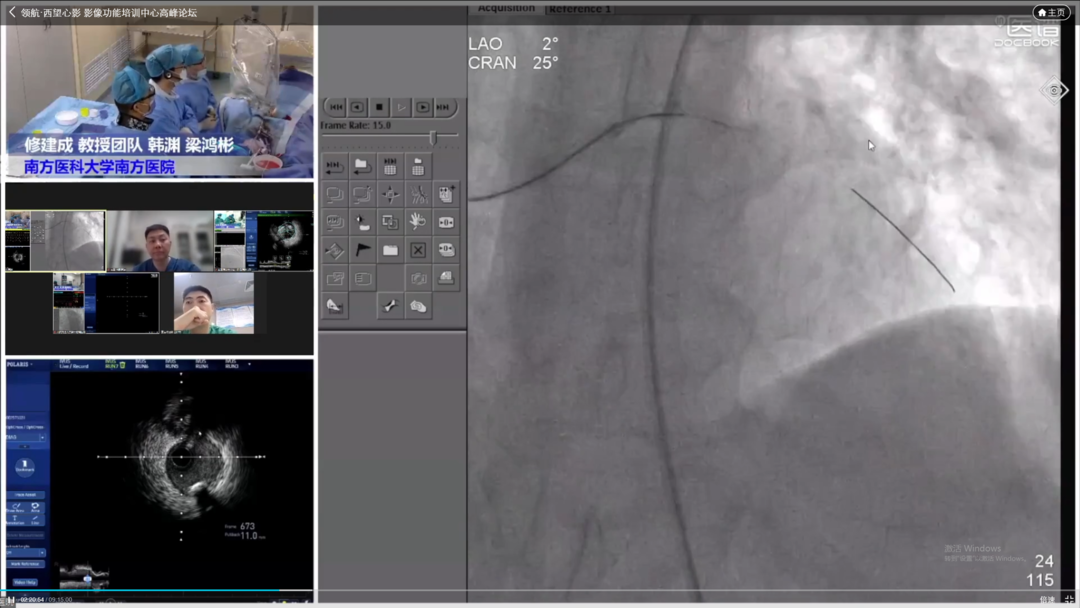

COE卓越中心成立旨在实现头部、地市、县域各医疗中心的联动,实现远程会诊与指导交流。疫情虽然隔绝各地区线下交流,但技术持续发展,远程需求快速增长,必将成为未来发展大趋势。其次希望通过COE中心将多年发展的影像数据进行收集整理发掘更多价值。第三是标准化培训体系建立,既可开展线上远程教学又可在疫情缓解时线下手把手教学,实现上下实时互动。波士顿科学始终对国内影像学与功能学技术的发展充满信心,也希望在波科本土化的进程中,与中国专家共同促进技术创新,服务广大中国患者。会议期间,四川大学华西医院、西安交通大学第一附属医院、南方医科大学南方医院、新疆医科大学第一附属医院、宁夏医科大学总医院心脑血管病医院联袂呈现17例高质量手术直播,所有与会专家各抒己见,畅谈影像技术实战应用。其中四川大学华西医院何森教授带来IVUS指导下LAD重度狭窄伴钙化手术一例。陈勇教授演示一例IVUS指导下的多支血管病变手术;周名纲教授演示一例一月内二次处理的多支病变复杂手术。王勉教授演示一例IVUS指导下逆向开通LAD慢性次全闭塞手术;黄宝涛教授带来了一例IVUS指导下旋磨处理LAD严重钙化病变;李晨教授演示了一例IVSU指导下开通无残端CTO病变的病例。西安交通大学第一附属医院郭宁、张勇教授团队带来造影剂过敏患者PCI治疗,通过IVUS不仅明确病变部位的斑块性质及血管解剖情况,同时确定支架落脚点位置及支架选择。最后在IVUS指导下顺利植入三枚支架,充分展示IVUS对指导低造影剂PCI的临床价值。由南方医科大学南方医院修建成、韩渊、梁鸿彬教授团队带来IVUS指导前降支CTO无残端的病例则先后在对角支、间隔支行IVUS找到前降支开口残端,同时IVUS显示,前降支开口后走行与间隔支夹角较小,近乎平行走行。明确解剖特点后果断决定逆向策略,最终在IVUS指导下,逆向导丝成功进入前降至病变部位远端建立导丝轨道,手术迎来完美结果。宁夏医科大学总医院心脑血管病医院仇玉民、胡光欣教授带来一例右冠CTO病例,残端似乎存在微通道,本计划行ADR,首次尝试正向开通时选择波士顿科学Sentai导丝家族Fighter导丝,仇教授提到该款导丝操控性极佳,头端硬度1.5g,外径0.09"直接通过微通道越过病变部位到达右冠远端,成功建立轨道。正确选择导丝取得开门红后,在IVUS指导下顺利植入一枚支架,迅速完成了这例颇具挑战的手术。精彩的手术演示不仅深度传递腔内影像学与功能学指导下优化PCI治疗的理念,更详细阐述IVUS的规范操作和读图技巧,在理论与实践两方面,实现知行合一。